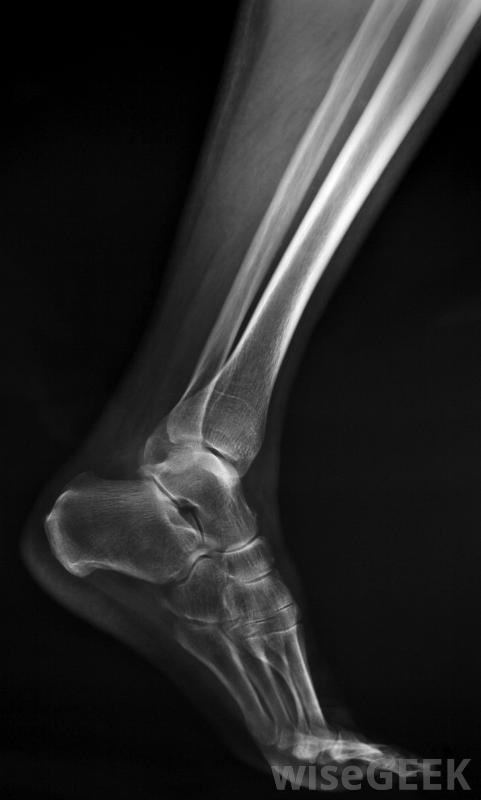

脛骨應力性骨折的癥狀是什么(Symptoms of a Tibial Stress Fracture)?

脛骨應力性骨折發生在小腿肌肉前部的小腿骨上,是跑步者因過度使用而造成的骨骼損傷,這種情況在跑步者中很常見。其主要癥狀是脛骨疼痛,通常表現為逐漸加重的疼痛。其他癥狀包括沿脛骨的腫脹和小腿肌肉的壓痛然而,疼痛通常在休息時不會發生,導致脛骨應力性骨折的因素有很多,如過度訓練、營養不良,低水平的睪酮或雌激素。脛骨應力性骨折在跑步者中很常見。重復性脛骨過載和應力使其無法自然愈合并導致脛骨應力性骨折。由于反復的創傷,骨骼無法吸收沖擊力,從而削弱了骨骼。診斷包括徹底的病史、體格檢查和可能的骨骼掃描。X光通常不顯示一種骨應力性骨折,盡管連續的X光片可以顯示出骨骼試圖愈合的部位。X光片通常不會顯示脛骨應力性骨折脛骨應力性骨折最常見的癥狀是脛骨下半部局部疼痛,與脛骨夾板疼痛相似它通常開始時是隱痛或輕微刺激,并隨著持續使用腿部而逐漸加重,如步行、跑步或運動,疼痛逐漸加重。一般來說,脛骨疼痛在休息時消失,盡管情況嚴重,即使不使用腿也可以繼續。在這種情況下,這種疼痛會嚴重到使人無法行走。脛骨應力性骨折的另一個癥狀是由于肌肉、肌腱發炎而沿脛骨腫脹,以及骨骼周圍的組織。脛骨受到擠壓時可能會受傷或骨折部位出現肌肉壓痛。在某些情況下,脛骨應力性骨折也可能導致小腿疼痛或膝關節疼痛。有幾種因素會導致脛骨應力性骨折的疼痛和其他癥狀。過度訓練,如進行強度過大或過大的運動量,都會導致疼痛重復性壓力導致脛骨損傷。營養不良和鈣鎂缺乏會導致骨骼健康狀況不佳,并增加壓力性骨折的風險。低水平的睪酮或雌激素也是危險因素,以及長期使用某些藥物,如類固醇脛骨疼痛是脛骨應力性骨折最常見的癥狀。